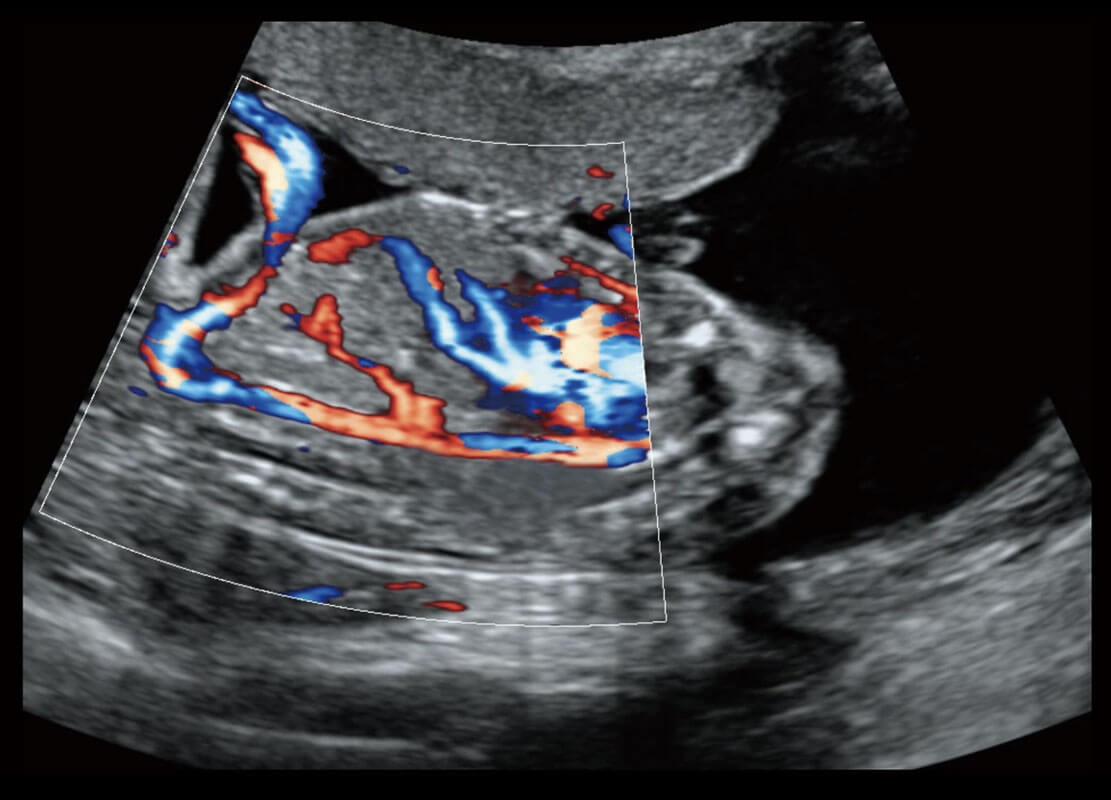

P60搭載一系列胎兒心臟成像技術(shù),實現(xiàn)精細的胎兒心臟評估。

四腔心血流